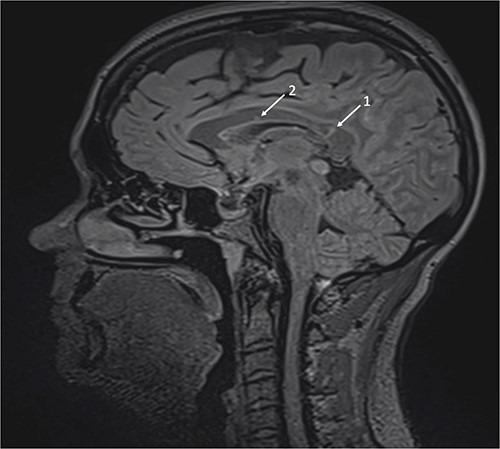

Repeat MRI at this time demonstrated several small T2 hyperintense foci within the deep white matter tracts of both cerebral hemispheres, the corpus callosum, and the thalamic and basal ganglion in addition to the typical linear ‘spoke’ lesions within the roof of the corpus callosum (Fig. 2). Fluorescein fundus angiography demonstrated multiple BRAOs and arterial wall hyperfluorescence (AWH) in the infratemporal region of the right eye, while the examination of the left eye remained normal (Fig. 3).

Brain magnetic resonance imaging (MRI) with sagittal T2 FLAIR illustrating linear ‘spoke’ (1) and T2 hyperintense lesions (2) in the corpus callosum.